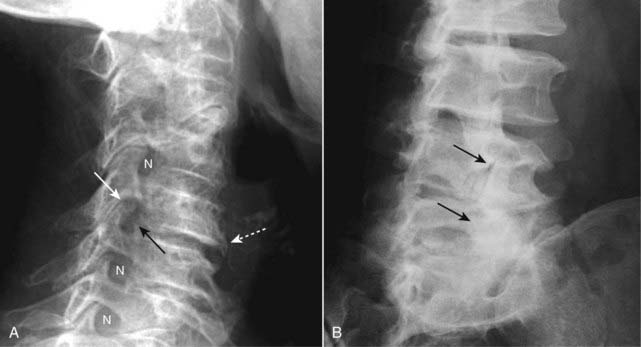

imageIn the cervical spine, osteophytes that develop at the uncovertebral joints can produce protrusions of bone into the normally oval-shaped neural foramina, which are visualized on conventional radiographs taken in the oblique projection (Fig. 24-8A).

image There is usually a complex interrelationship between degenerative disk disease and facet arthritis such that the two frequently occur together. The osteophytes formed by osteoarthritis of the facet joints may also encroach on the neural foramina and produce radicular pain.

image In the lumbar spine, facet osteoarthritis may cause narrowing and sclerosis of the facet joints, best seen on oblique views of the spine. Facet arthritis is easier to visualize on CT scans of the spine than on conventional radiographs, and actual nerve compression is easier to visualize on MRI of the spine (Fig. 24-8B).

Figure 24-8 Uncovertebral osteophytes and facet arthritis.

A, In the cervical spine, osteophytes may develop at the uncovertebral joints (solid black arrow) producing bony protrusions into the normally oval-shaped neural foramina (N), in this radiograph taken in the oblique projection. Osteophytes at the uncovertebral joints are frequently associated with both degenerative disk disease (dotted white arrow) and osteophytes of the facet joints (solid white arrow). B, There is sclerosis and osteophyte formation involving the lower facet joints of the lumbar spine (solid black arrows) representing facet arthritis.